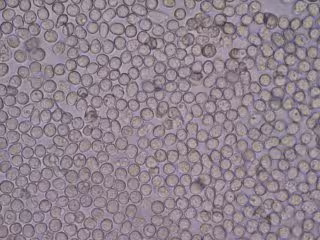

Linfocitos

Linfocitos - BOBJGALINDO/WIKIMEDIA COMMONS - Archivo